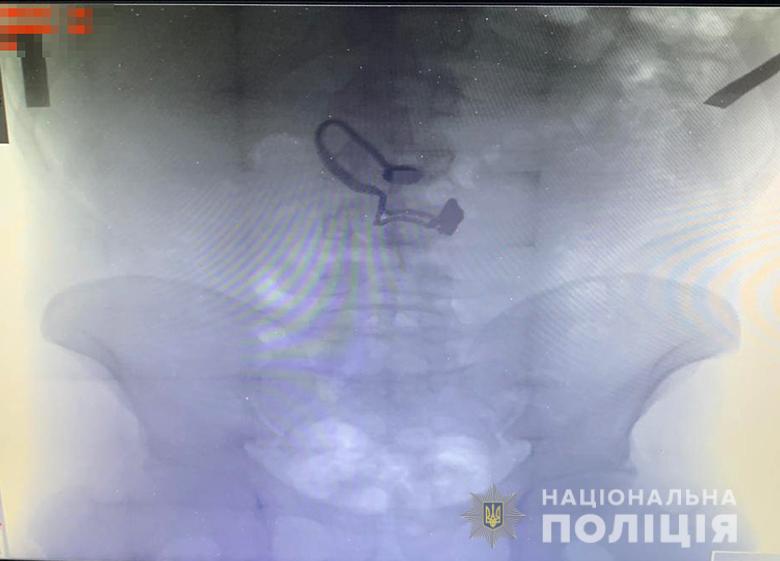

"Во время медосмотра на рентген-снимке задержанного врачи обнаружили украшение", - сообщают в полиции.